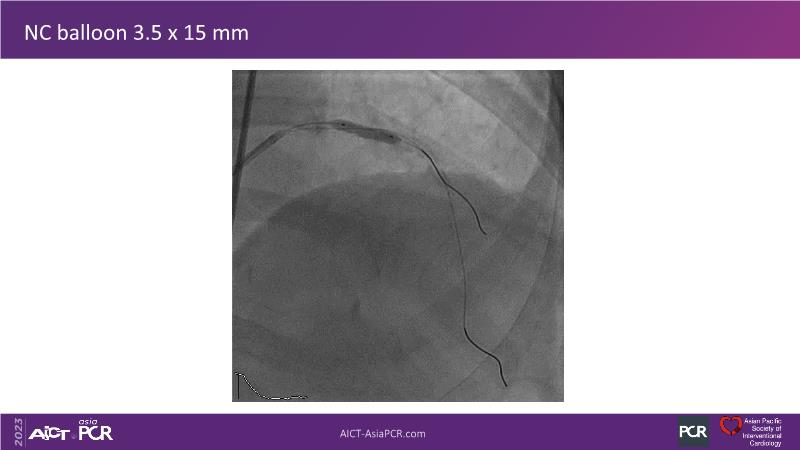

This session is recommended for you if you are seeking insights into the advantages of using IVUS imaging over visual assessment for better outcomes in left main bifurcation procedures. Discuss with experts the benefits of using RotaCUT in lesion preparation for left main bifurcation and explore the impact of high radial strength stents on the procedure's success.

• To see advantages of RotaCUT as part of lesion preparation in left main bifurcation